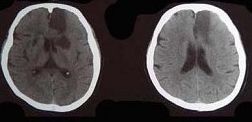

脑梗死 瘫痪 痉挛性瘫痪

最强考题第一期: 每天4道题,医学轻松知,奖励不停拿,各位联友抓紧时间作答吧~ 【更题时间】周一、周三、周五 【活动须知】每周三期活动,每期活动推出4道最强考题,每道题1分,每周累计分数最多(最高12分)的联友即有机会获取奖励; 当分数相同者,根据二者的答题时间比较,即二者分数相同,较早时间回答的联友胜。 【活动奖励】第一名:50元红包奖励 第二名:30元红包奖励 第三名20元奖励 【获奖名单】每周获奖名单将在次周周一同步更新 第1题:颅内压增高致脑神经麻痹多见于() A.滑车神经 B.展神经 C.动眼神经 D.听神经 E.面神经 第2题:有关楔束,哪项说法正确() A.贯穿脊髓后索全长 B.传导同侧下肢浅感觉 C.传导对侧下肢本体觉 D.上升至同侧楔束核换元 E.以上都不对 第3题:右下肢痉挛性瘫痪,右瞳孔缩小,左侧胸、腹、下肢的痛、温觉及右侧精细触觉丧失 而双上肢正常,则病变部位可能在() A.延髓左侧半横断 B.延髓第1~4胸节右半横断 C.延髓第1~4颈节右半横断 D.延髓第5~8颈节右半横断 E.左侧大脑皮质 第4题:头颅CT出现如图所示脑梗死,该病灶最可能是下列哪条阻塞引起() A.大脑前动脉主干 B.颈内动脉主干 C.大脑中动脉主干 D.脉络膜前动脉 E.豆纹动脉